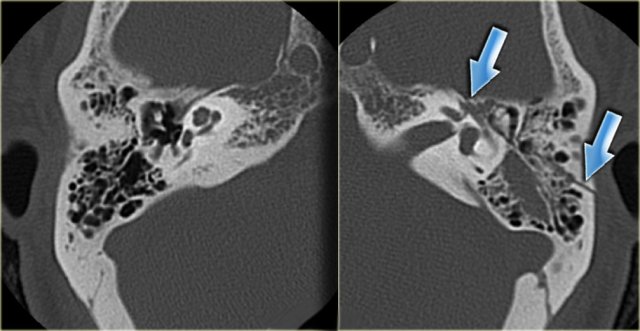

On the left images of a 14-year old boy with bilateral sensorineural hearing loss.

Calcification of superior semicircular canal on the left (yellow arrow).

Right ear for comparison (blue arrow).

On the left coronal images of the same patient.